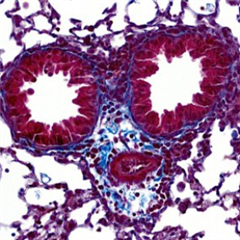

Malgré les avancées dans le traitement des patients atteints des formes les plus sévères d’asthme, des progrès restent à faire car la moitié des patients traités ne répond pas ou insuffisamment. L’identification de nouvelles cibles thérapeutiques reste donc un défi. Dans un article publié dans Nature Communications, des scientifiques de l'Institut toulousain des maladies infectieuses et inflammatoires (INFINITy) démontrent, chez la souris, qu’il est possible de cibler spécifiquement les lymphocytes Th2, principaux responsables de l’’inflammation de type2.